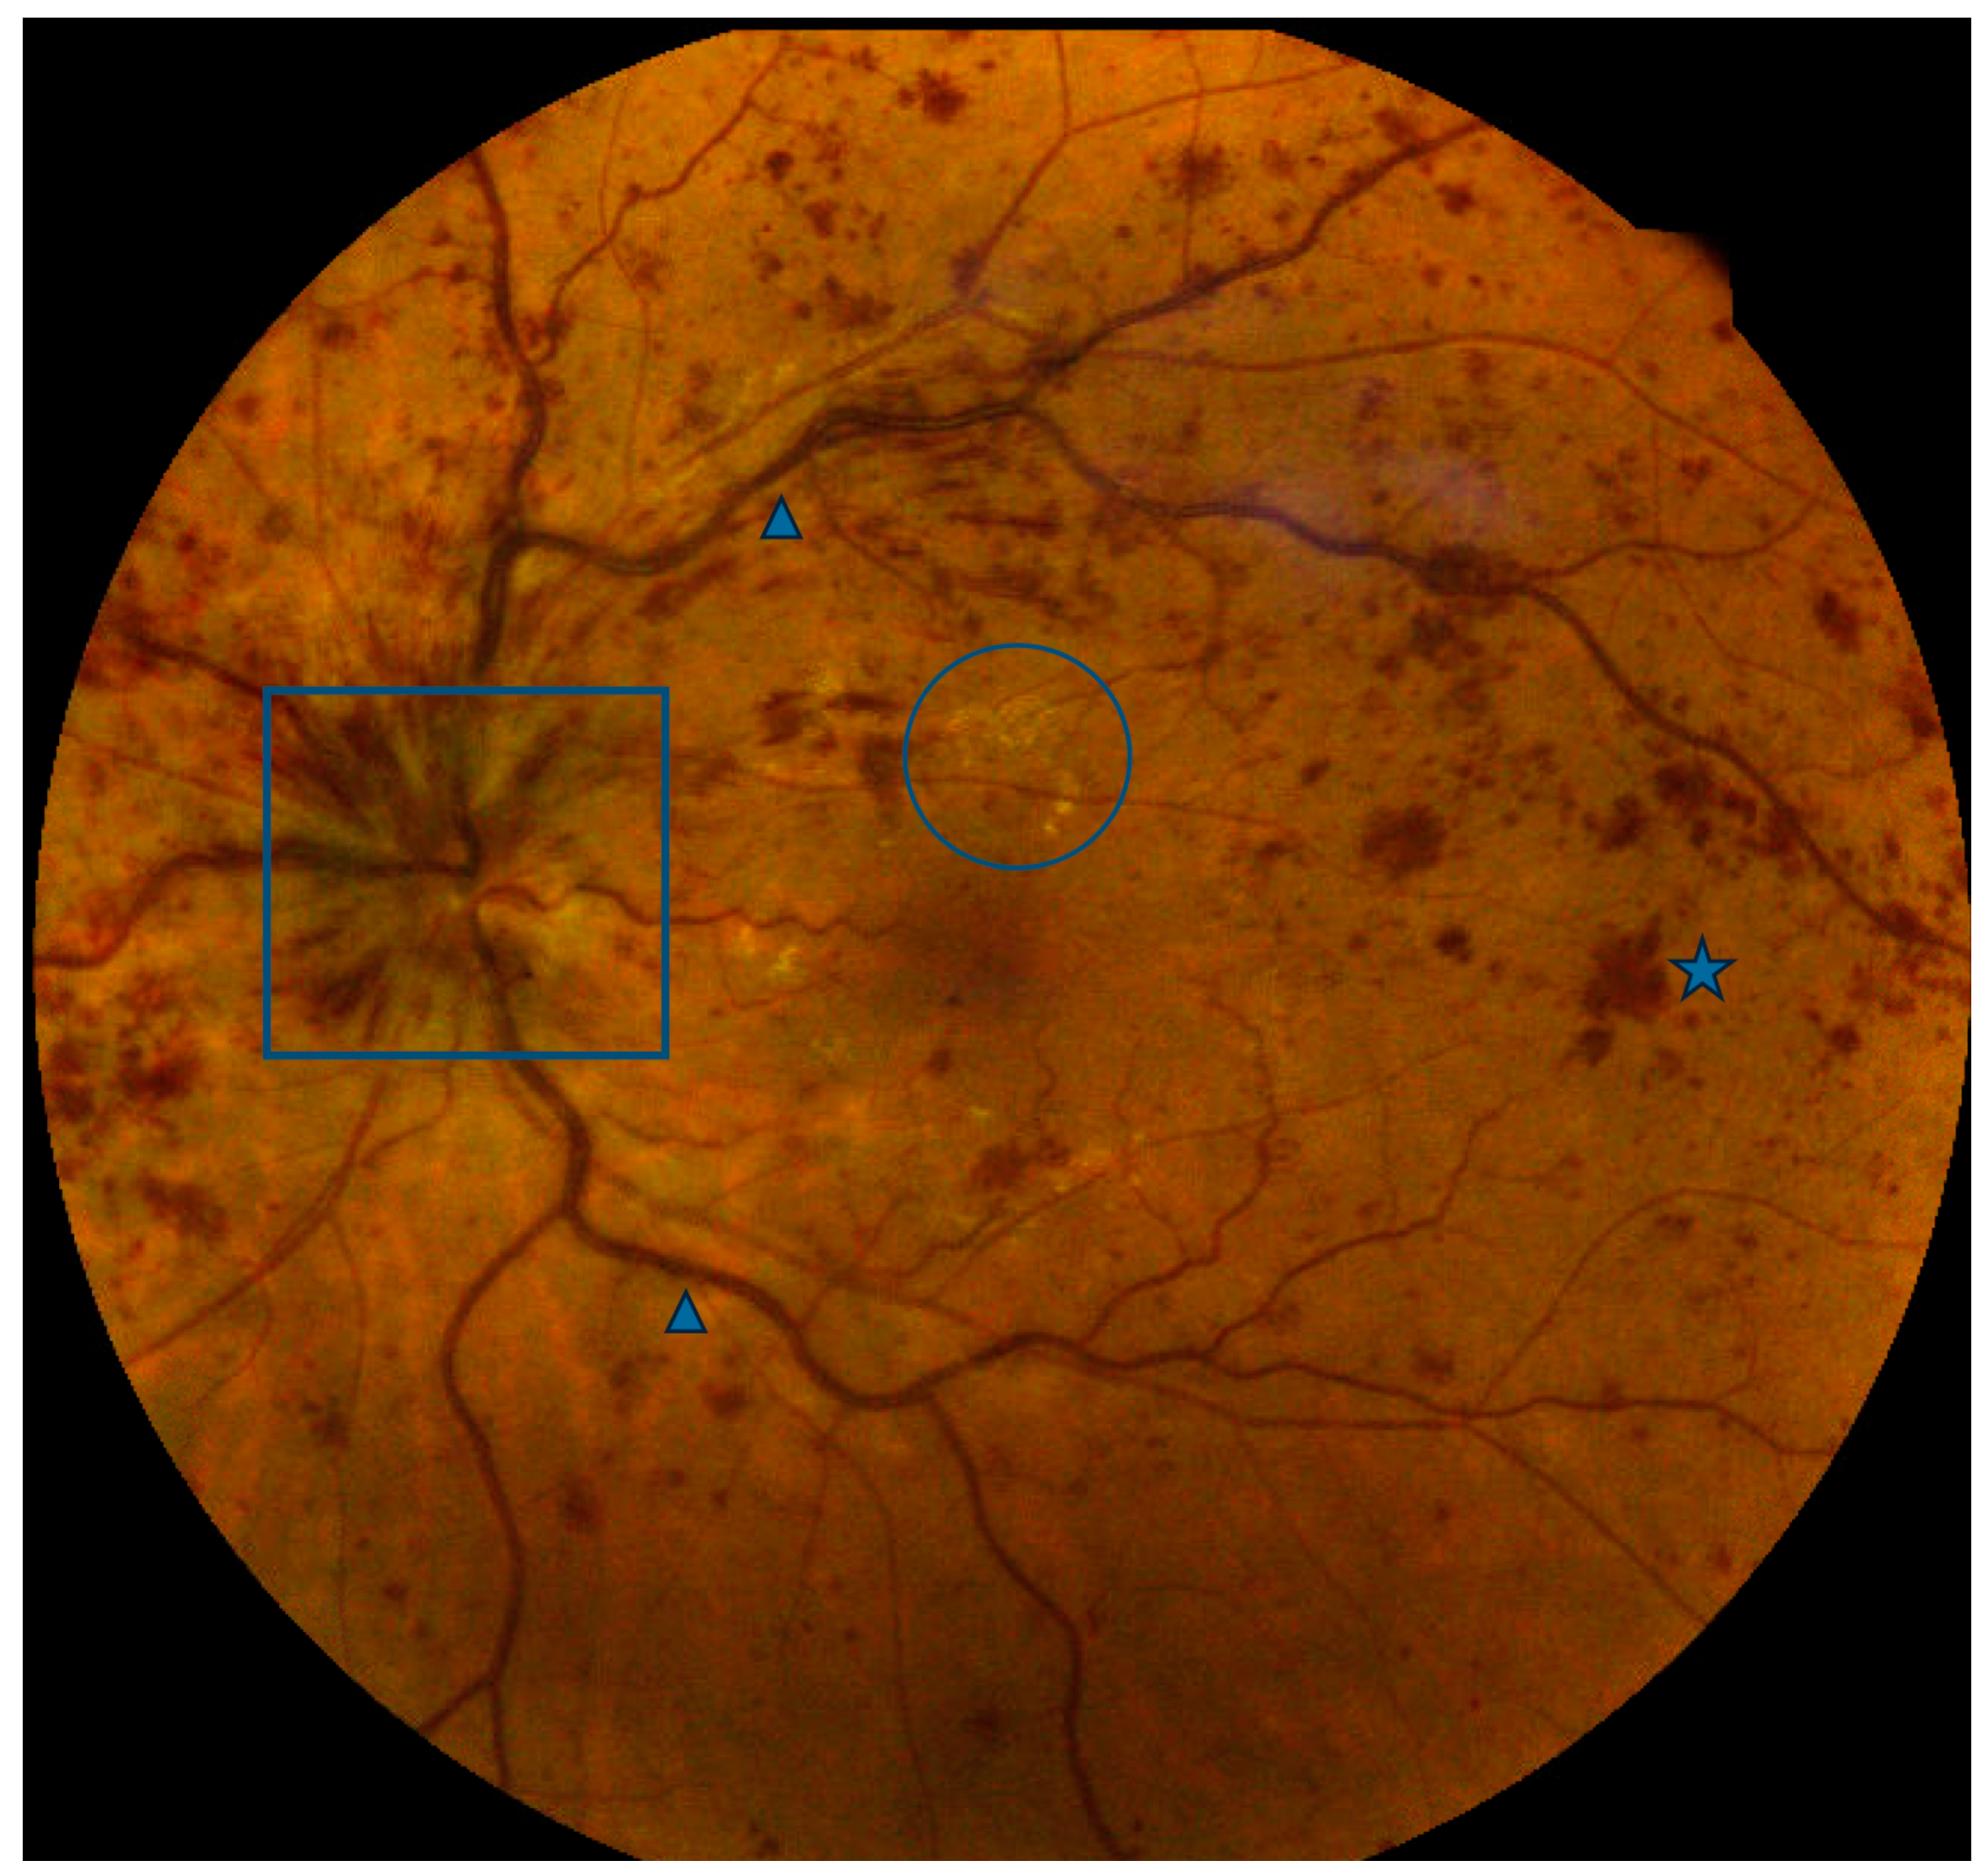

3.1.4. Age-Related Macular Degeneration: Subretinal Drusenoid Deposits

- Agrón, E.; Agrón, E.; Domalpally, A.; Domalpally, A.; Cukras, C.A.; Cukras, C.A.; Clemons, T.E.; Clemons, T.E.; Chen, Q.; Chen, Q.; et al. Reticular Pseudodrusen: The Third Macular Risk Feature for Progression to Late Age-Related Macular Degeneration: Age-Related Eye Disease Study 2 Report 30. Ophthalmology 2022, 129, 1107–1119. [Google Scholar] [CrossRef] [PubMed]

- Thomson, R.J.B.; Chazaro, J.B.; Otero-Marquez, O.; Ledesma-Gil, G.; Tong, Y.; Coughlin, A.C.B.; Teibel, Z.R.; Alauddin, S.; Tai, K.B.; Lloyd, H.B.; et al. Subretinal drusenoid deposits and soft drusen: Are they markers for distinct retinal diseases. Retina 2022, 42, 1311–1318. [Google Scholar] [CrossRef]

- Cymerman, R.M.; Skolnick, A.H.; Cole, W.J.; Nabati, C.; Curcio, C.A.; Smith, R.T. Coronary Artery Disease and Reticular Macular Disease, a Subphenotype of Early Age-Related Macular Degeneration. Curr. Eye Res. 2016, 41, 1482–1488. [Google Scholar] [CrossRef]

- Liang, C.; Wang, N. Subretinal Drusenoid Deposits and Lower Serum High-Density Lipoprotein Cholesterol Levels Possess Latent Relation to Cardiovascular Disease and Can Be a Feasible Predictor. Comput. Math. Methods Med. 2022, 2022, 3135100. [Google Scholar] [CrossRef]